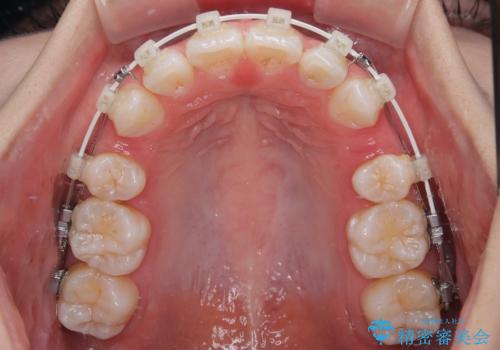

- 矯正装置

- 審美装置

- 口を閉じたときに飛び出してしまう上顎前歯を気にして来院された患者様です。

下顎はデコボコが気になっていたため、上下左右第一小臼歯4本を抜去して、ワイヤー装置にて口元の突出感を改善するよう矯正治療を行うこととしました。